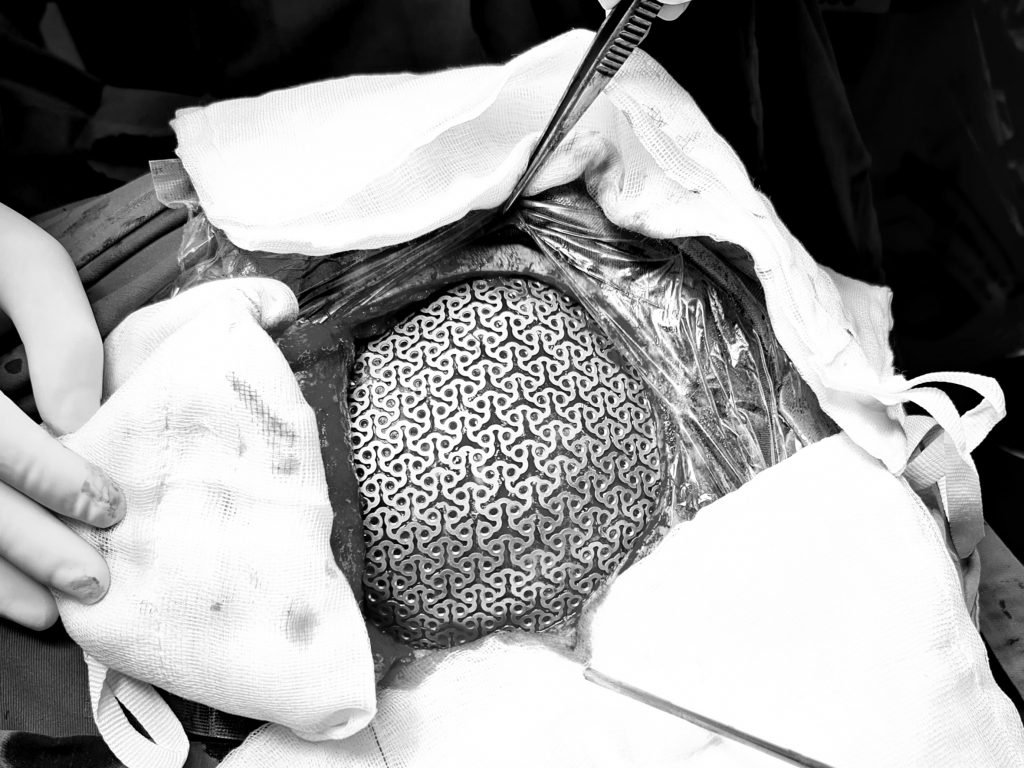

Quy trình phẫu thuật cơ bản

Phẫu thuật ghép sọ thường bao gồm các bước:

- Rạch da theo sẹo mổ cũ, bóc tách để bộc lộ vùng khuyết sọ

- Đặt lại mảnh xương sọ và cố định bằng nẹp vis hoặc ghim

- Trường hợp không có xương tự thân: sử dụng vật liệu nhân tạo (lưới Titanium, cement…)

- Khâu treo màng cứng

- Đặt dẫn lưu và đóng vết mổ

Công nghệ in 3D trong ghép mảnh sọ Titanium

Việc tạo hình chính xác khuyết hổng xương sọ luôn là thách thức lớn. Nếu tạo hình không phù hợp, mảnh ghép có thể bị lệch, cong vênh và không khớp với hộp sọ.

Công nghệ in 3D đã giải quyết vấn đề này bằng cách:

- Chụp CT đa dãy để tạo dữ liệu 3D vùng khuyết sọ

- Xử lý dữ liệu để thiết kế mảnh ghép theo đúng hình dạng thực tế

- Sản xuất mảnh ghép bằng vật liệu phù hợp (Titanium, PEEK, xi măng sinh học…)

Nhờ đó, mảnh ghép:

- Khớp chính xác với cấu trúc hộp sọ

- Đảm bảo tính thẩm mỹ cao

- Tăng hiệu quả điều trị

Hiện nay, Trung tâm Kỹ thuật cao phối hợp với Khoa Phẫu thuật Thần kinh – Bệnh viện Đa khoa Xanh Pôn đã triển khai thường quy kỹ thuật này, đặc biệt là ghép mảnh sọ 3D Titanium, mang lại kết quả an toàn và tối ưu thẩm mỹ.